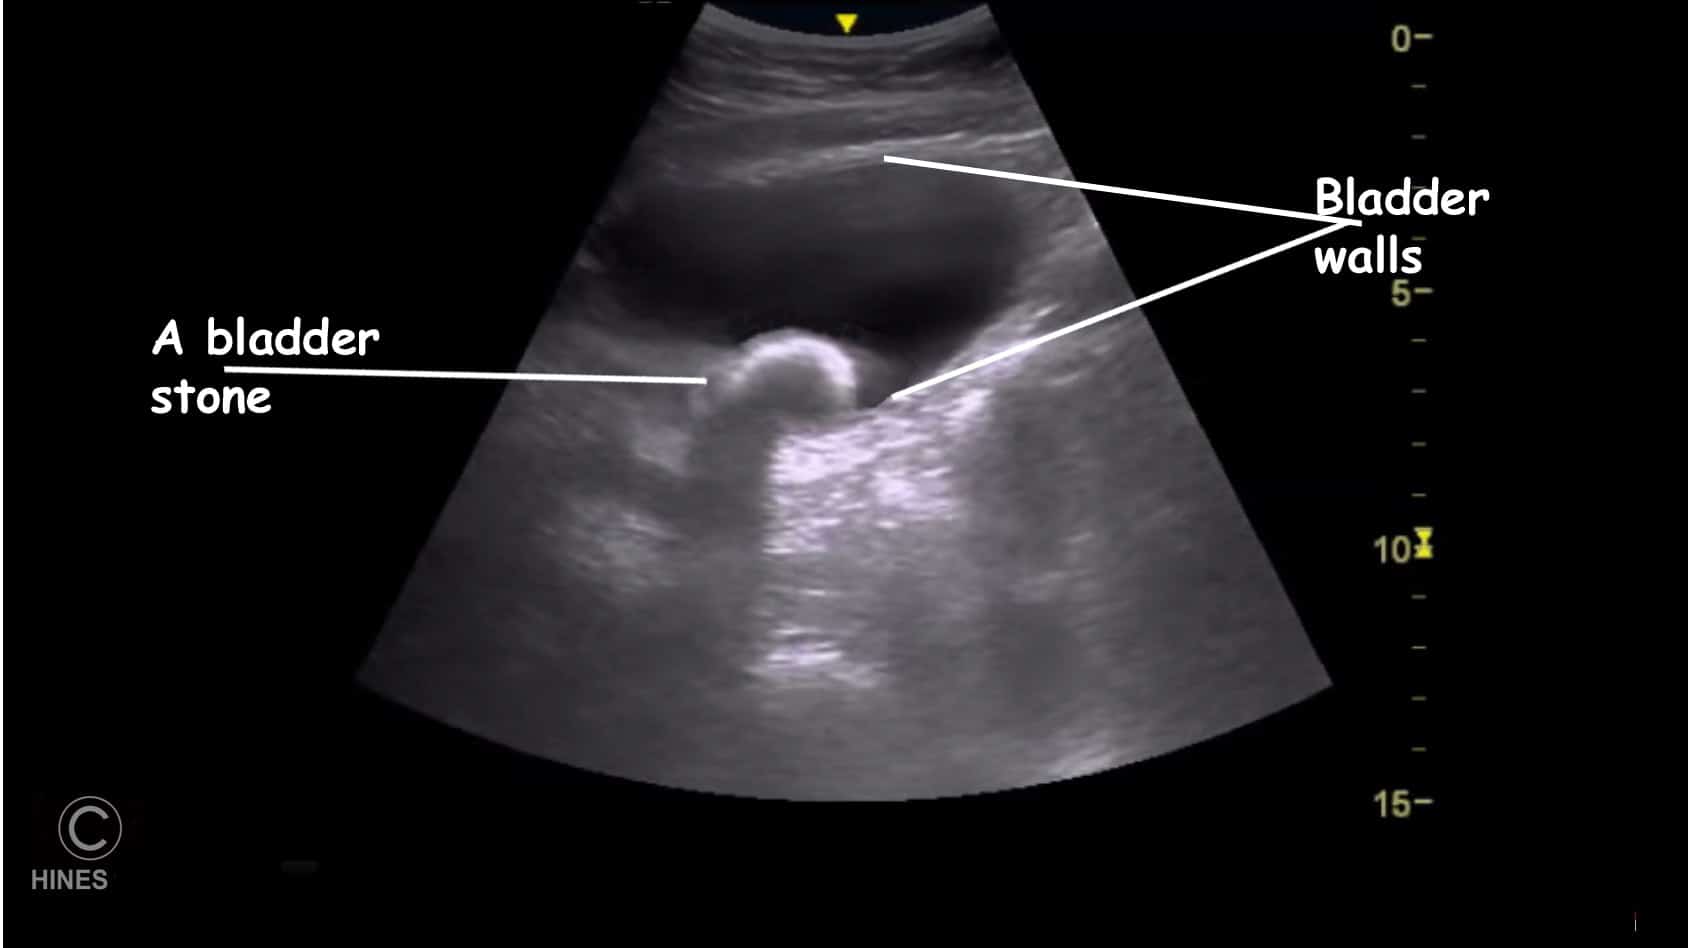

Ultrasound

An ultrasound examination often confirms a stone’s presence as well. (read here) Stones less than 3 mm in diameter can be very difficult to see. X-rays and ultrasound also tell your veterinarian the urgency of your pet’s situation. Bladder stones that have a diameter greater than that of your dog’s urethra are unlikely to enter the urethra and block the flow of urine. Those considerably smaller will likely pass out with the urine. But those that are approximately the same diameter as your dog’s urethra could block the flow of urine if they get stuck in the pet’s urethra on their way out – causing a medical emergency that could happen at any time. (read here) If your veterinarian suspects Cushing’s disease as a predisposing factor, test for that condition might be indicated as well.